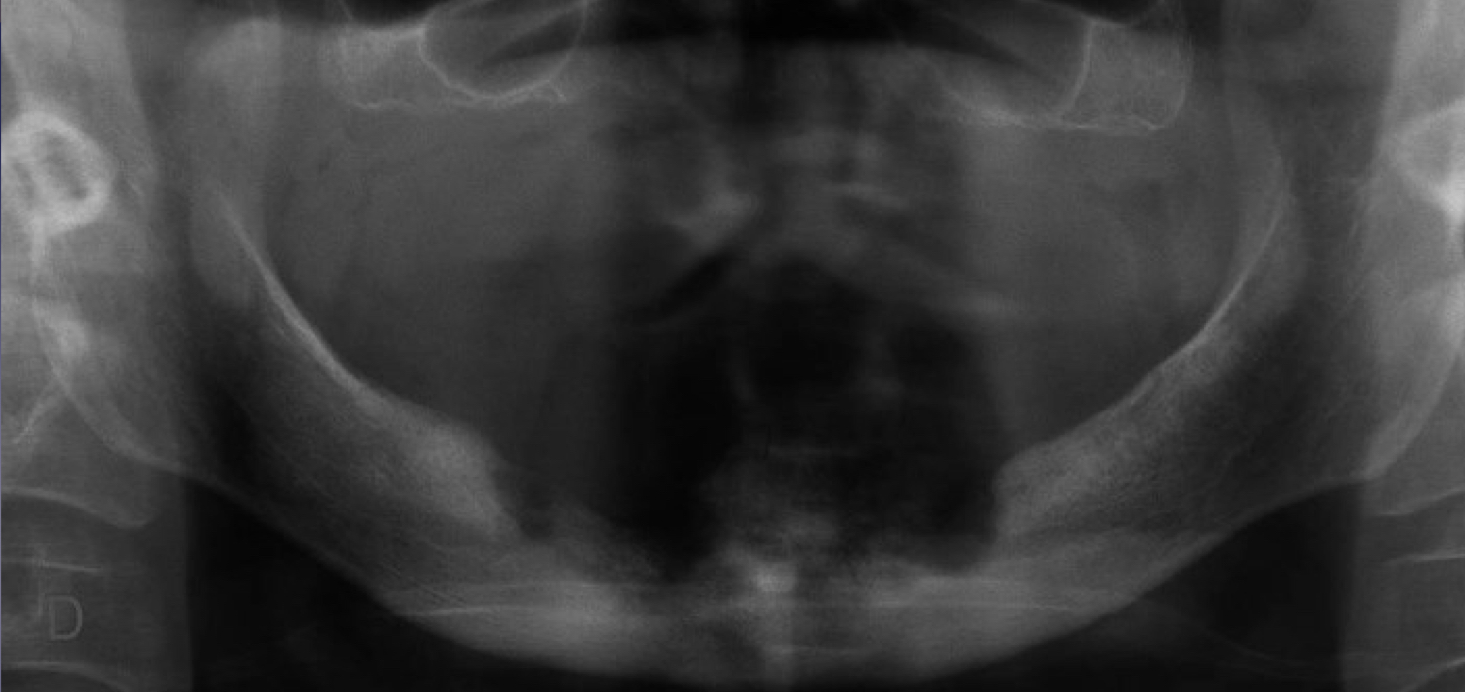

which type of chronic osteomyelitis?

primary response: proliferation reaction

sclerotic appearance of involved bone

subperiosteal bone deposition

slight jaw enlargement

involves large segment of jaw

diffuse sclerosing osteomyelitis

diffuse sclerosing osteomyelitis, young pt

diffuse sclerosing of left angle-ramus of mandible = L more radiopaque than R

which chronic osteomyelitis?

diffuse sclerotic bone

case of SAPHO syndrome bc wrist and mandible involved